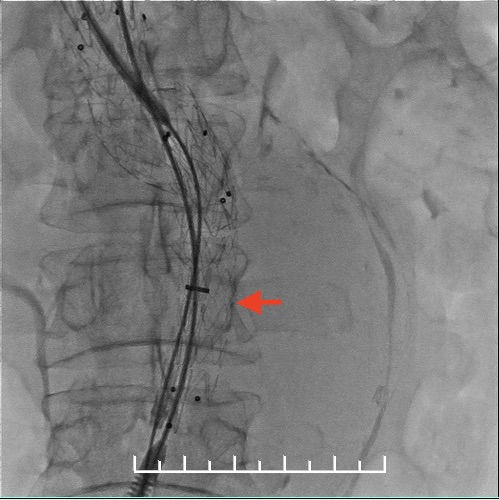

使用全穿刺技术(Preclose技术),建立双侧股动脉及右侧肱动脉入路。“全身像”显示:瘤颈成角约90度,左侧髂总动脉钙化扭曲严重,双侧髂内动脉显影,左侧髂内动脉瘤。

栓塞左侧髂内动脉。箭头处可见髂总动脉钙化扭曲明显,进出导管十分困难。